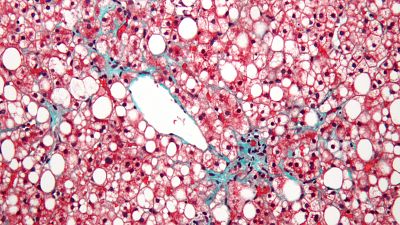

Con el más que loable reto de eliminar la hepatitis C antes del 2021, se acaba de presentar, en el marco del 42º Congreso de la Asociación Española para el Estudio del Hígado, que se celebró del 15 al 17 de febrero de este 2017, con la asistencia de más de 600 especialistas en toda España, la Alianza para la Eliminación de las Hepatitis Víricas en España.

El tratamiento actual con antivirales directos, cambio revolucionario en el tratamiento del VHC en los últimos años, confirma en la práctica clínica real sus excelentes resultados, con una tasa de curación superior al 95% y un excelente perfil de seguridad.